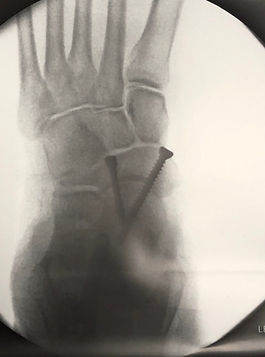

Metacarpal Fracture